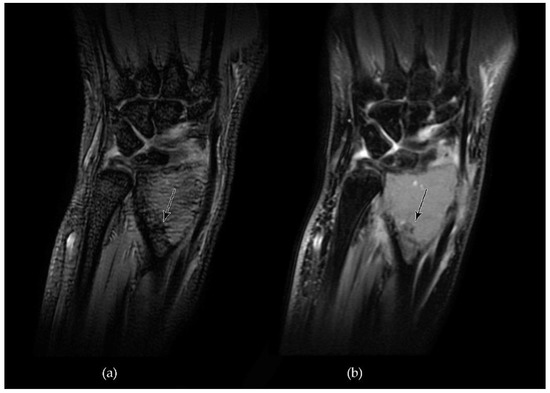

- Engellau, J.; Seeger, L.; Grimer, R.; Henshaw, R.; Gelderblom, H.; Choy, E.; Chawla, S.; Reichardt, P.; O’Neal, M.; Feng, A.; et al. Assessment of denosumab treatment effects and imaging response in patients with giant cell tumor of bone 11 Medical and Health Sciences 1103 Clinical Sciences. World J. Surg. Oncol. 2018, 16, 191. [Google Scholar] [CrossRef] [PubMed]

- Oguro, S.; Okuda, S.; Sugiura, H.; Matsumoto, S.; Sasaki, A.; Susa, M.; Morioka, H.; Jinzaki, M. Giant cell tumors of the bone: Changes in image features after denosumab administration. Magn. Reson. Med. Sci. 2018, 17, 325–330. [Google Scholar] [CrossRef]

- Alothman, M.; Althobaity, W.; Asiri, Y.; Alreshoodi, S.; Alismail, K.; Alshaalan, M. Giant cell tumor of bone following denosumab treatment: Assessment of tumor response using various imaging modalities. Insights Imaging 2020, 11, 41. [Google Scholar] [CrossRef] [PubMed]

- van Langevelde, K.; McCarthy, C.L. Radiological findings of denosumab treatment for giant cell tumours of bone. Skelet. Radiol. 2020, 49, 1345–1358. [Google Scholar] [CrossRef]

- Campanacci, L.; Sambri, A.; Medellin, M.R.; Cimatti, P.; Errani, C.; Donati, D.M. A new computerized tomography classification to evaluate response to Denosumab in giant cell tumors in the extremities. Acta Orthop. Traumatol. Turc. 2019, 53, 376–380. [Google Scholar] [CrossRef] [PubMed]